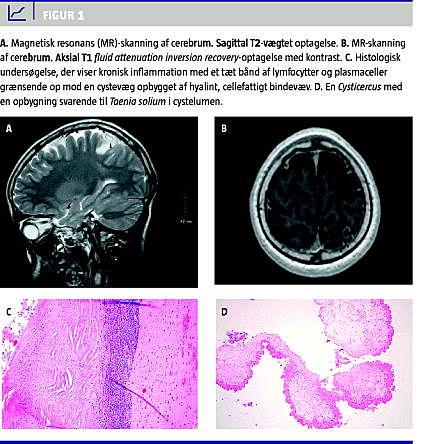

Patienten var tidligere testet negativ for hiv og hepatitis A, B og C. Han fik foretaget en magnetisk resonans-skanning af cerebrum, og den viste en solitær, ringopladende cystisk proces, der var beliggende subkortikalt i venstre parietallap (Figur 1 A og 1B).

Patienten blev opereret via en lille kraniotomi. Processen blev fridissekeret mikrokirurgisk og blev fjernet en bloc. En histologisk undersøgelse viste tegn til kronisk inflammation med et tæt bånd af inflammatoriske celler, der grænsede op mod en cystevæg. I cystelumen fandtes en Cysticercus med en opbygning svarende til Taenia solium (Figur 1C og 1D).